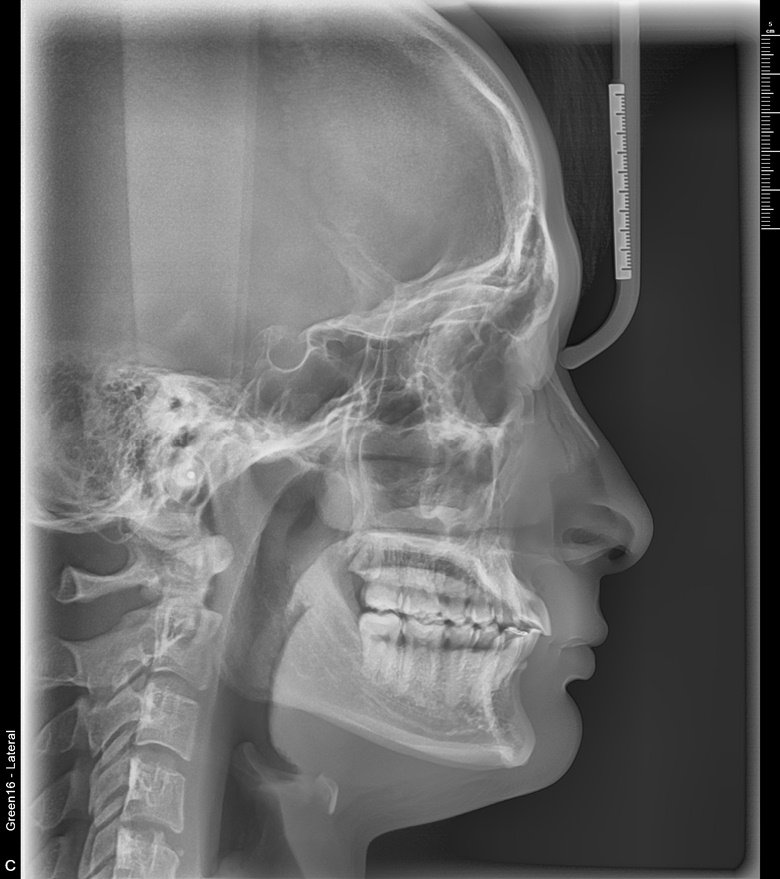

치료 전 사진입니다.